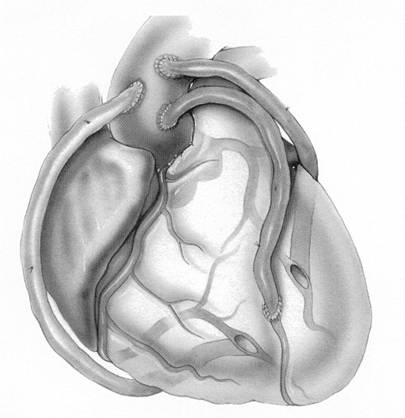

Ziel der Operation ist, jeder höhergradige Stenose an relevanten Coronarästen (Abb.1.) mittels Bypass zu überbrücken, es wird somit über arterielle oder venöse Bypässe in die zuvor minderversorgten Areale wieder ausreichend Blut transportiert (Abb. 2.). Triviale Äste können jedoch wegen ihres kleinen Durchmessers nicht versorgt werden. Der aortocoronare Mehrfachbypass unter Verwendung der Arteria thoracica interna (linke innere Brustarterie) ist heute absoluter Standard an jeder herzchirurgischen Klinik und die häufigste Herzoperation weltweit (Abb.3.).

Abb. 2. Schematische Darstellung eines Dreifachbypass mit Venen auf

drei große Herzkranzgefäße an der Vorder- und Hinterseite des Herzens.